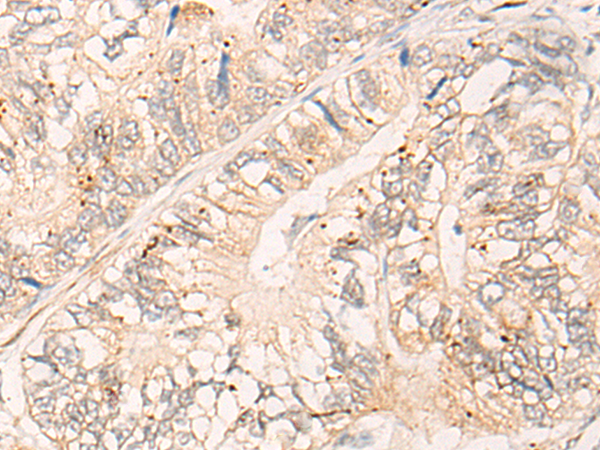

IHC positive control: |

Human liver cancer and Human gastric cancer |

IHC Recommend dilution: |

25-100 |